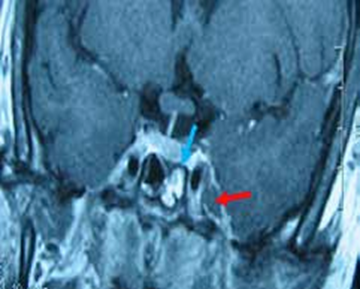

L’IRM abdominale objectivait des micronodules hépatiques iso-intenses T1-T2 évocateurs des séquelles tuberculeuse, sarcoïdose, autres.

Après l’intervention, nous avions constaté l’apparition d’adénopathies cervicales bilatérales ovalaires, dures et indolores dont la cytoponction confirmait la nature tuberculeuse des granulations hépatiques (Figure 8). La patiente a été mise sous traitement antituberculeux avec une surveillance clinique et biologique mensuelle. Nous avions constaté la disparition du syndrome inflammatoire au bout de quelques semaines, suivie de la disparition des adénopathies et des nodules hépatiques plus tard.